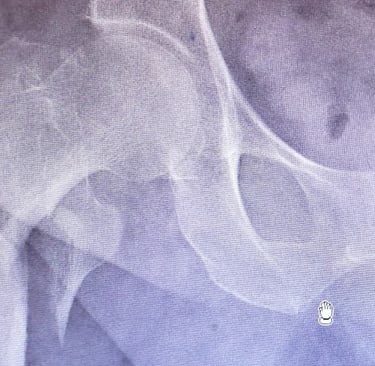

Diagnóstico

El diagnóstico se realiza mediante una evaluación clínica y estudios de imagen. El paciente suele presentar dolor intenso en la región de la cadera, incapacidad para caminar o cargar peso, y acortamiento o rotación externa de la pierna afectada. Las herramientas diagnósticas incluyen:

Radiografías: Permiten visualizar claramente la línea de fractura.